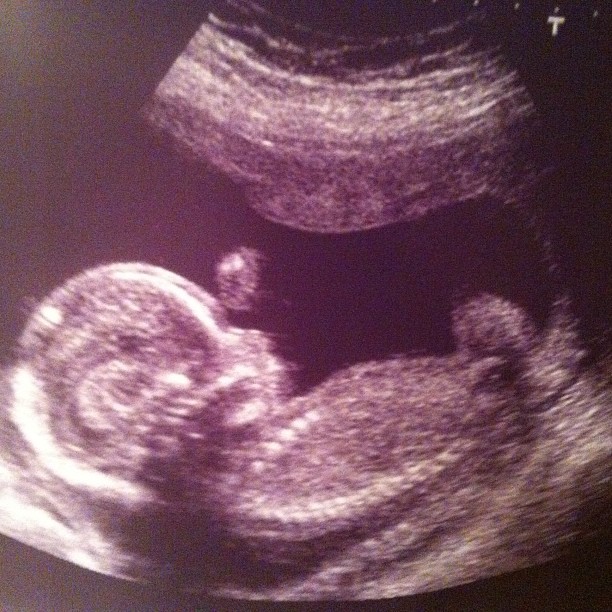

23 Oct It’s a…..

Turns out that this little miracle…

…is a…

I still can’t believe it…truly…I’m in a weird state of shock.

But…we’re so happy that bamino is a…

Anyhoo…baby looked healthy and that’s really all that matters.